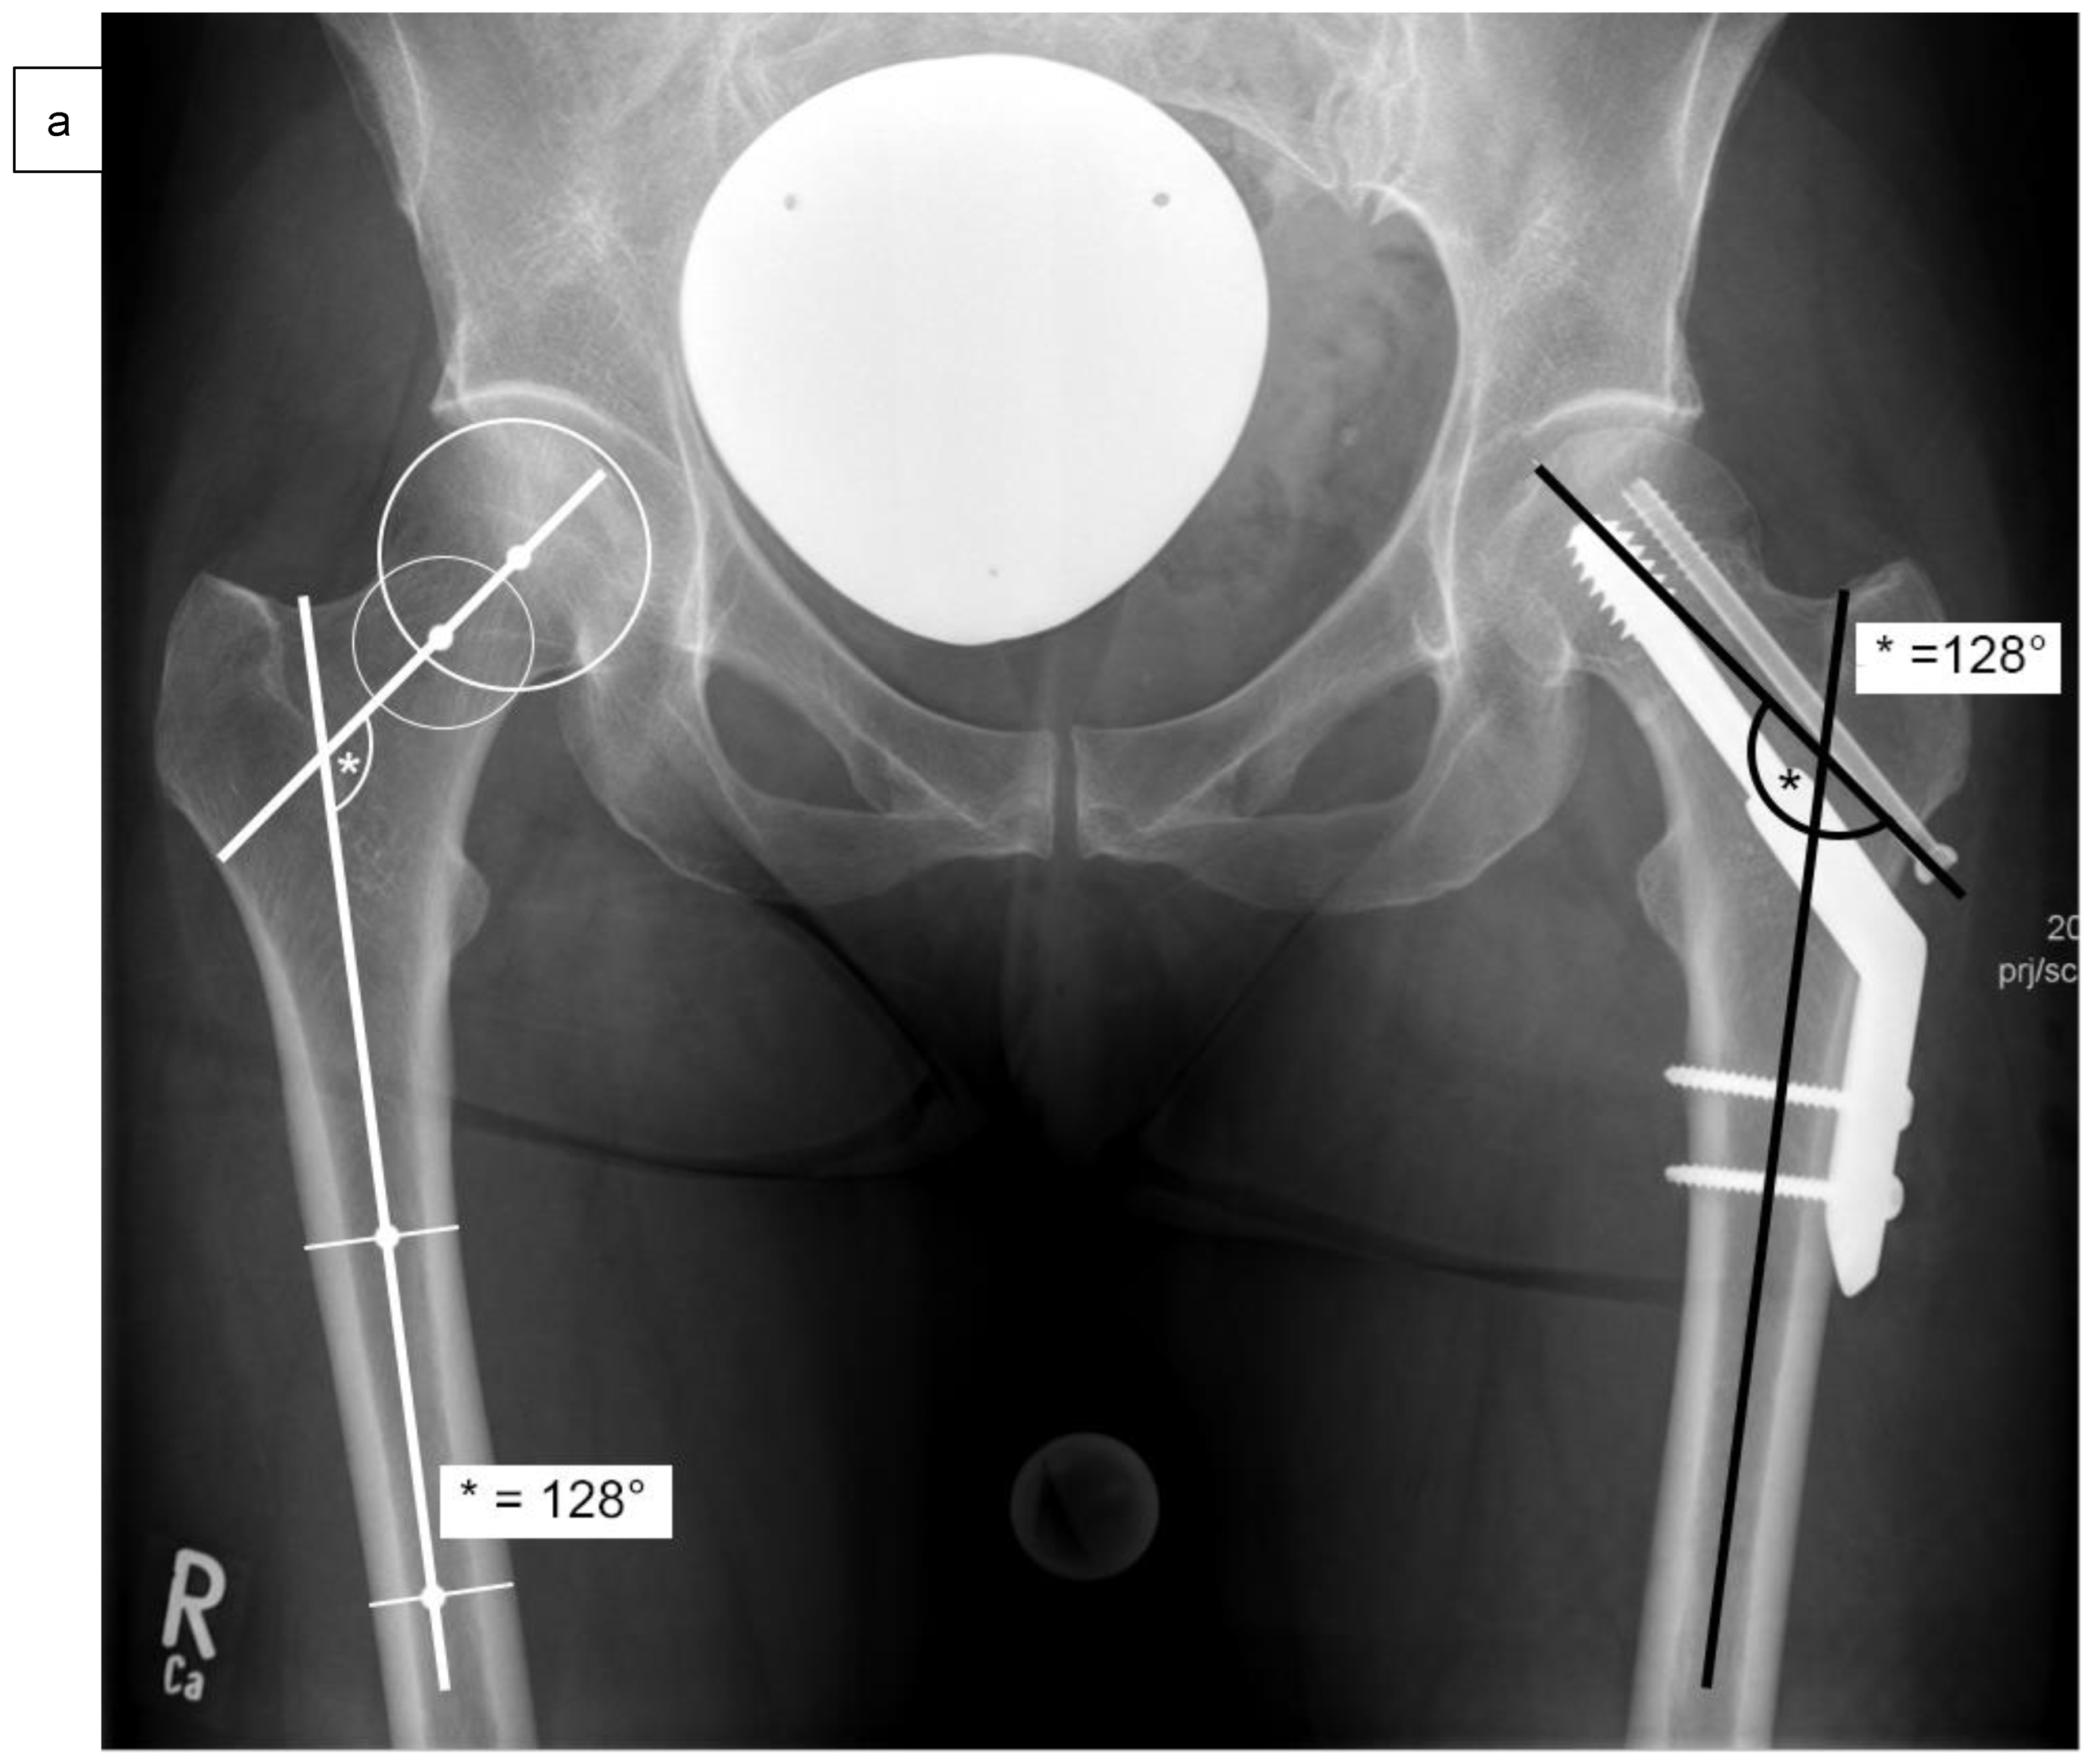

| Femoral neck angle 6 weeks postoperatively | 130.5 ± 3.8° | 142.8 ± 4.3° | 0.001 |

| Difference of the femoral neck angle 6 weeks postoperatively in comparison to the contralateral side | 1.2 ± 1.3° | 12.0 ± 4.2° | 0.001 |